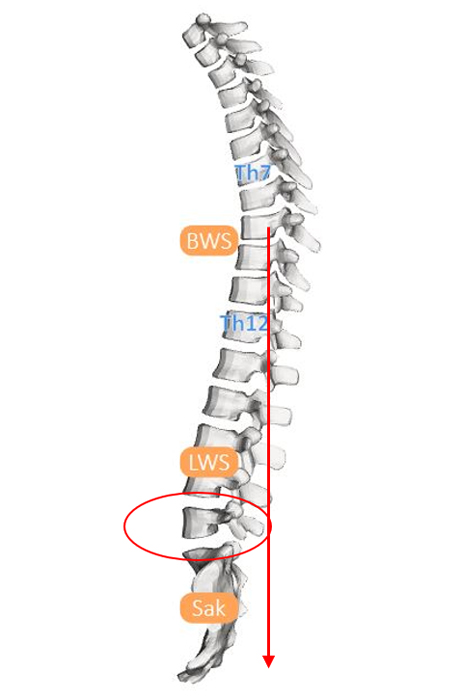

2. Beispiel – Wirbelverschiebung nach hinten

Auch bei dieser Aufnahme kann man Ähnlichkeiten zwischen der MRT-Aufnahme und der Konturdarstellung der Medi Mouse erkennen.

Bei dieser Wirbelsäulenform ist die normale Lordose der Lendenwirbelsäule nicht vorhanden, das Gegenteil ist der Fall, die Kyphose ist bis zum Kreuzbein verlängert.

Dies als Folge einer Rückverlagerung des Oberkörpers, was dazu führt, dass das eine Knicktendenz nach hinten entsteht und die Wirbelverschiebung nach hinten begünstigt.

Bei der Körperhaltungsanalyse kann man sehen, wie die Körpersegmente gegeneinander verschoben sind.

Von unten nach oben:

ist der Unterschenkel nach hinten gekippt

der Oberschenkel nach vorne

das Becken nach vorne verschoben

der Brustkorb gebeugt und nach hinten verschoben

der Schultergürtel und der Kopf nach vorne geschoben

Dieser Haltungstyp entspricht diesem Schema. Man kann sich vorstellen, dass eine solche geknickte Säule an den Knickungsstellen durch das Gewicht der Körpersegmente überlastet werden kann.